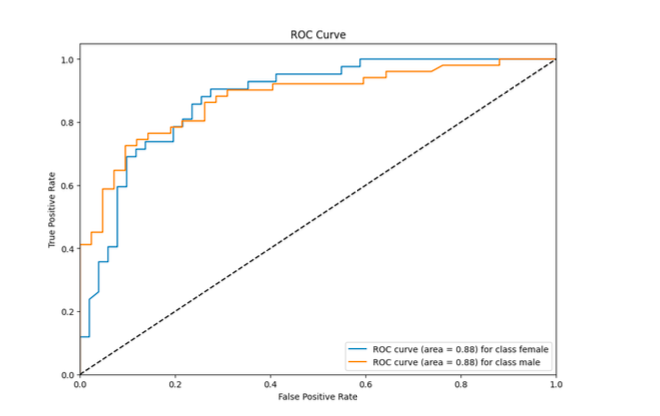

受试者工作特征 (ROC) 曲线:

ROC 曲线区域量化了模型区分类别的能力,如下所示:

女性的ROC曲线面积:0.88

男性的ROC曲线面积:0.88

女性和男性类别的ROC曲线面积均为0.88,表明该模型表现出强大的判别能力

实验结果表明,基于胸部X线图像的性别分类卷积神经网络(CNN)模型取得了令人满意的性能。女性和男性类别的准确率、召回率和 F1 分数指标都相当高,总体准确率为 78。